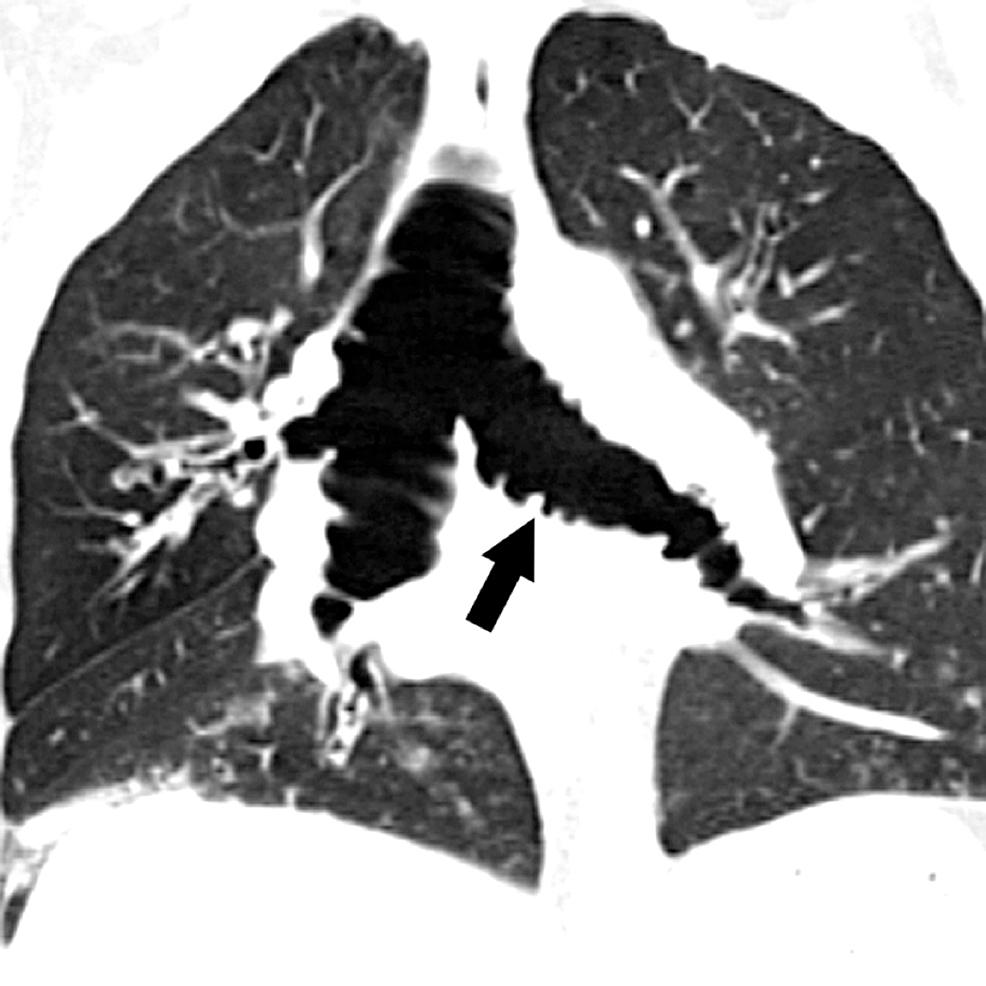

Tracheobronchomalacia Chest CT Acquired tracheomalacia. Paired Tracheobronchomalacia Life Expectancy tracheobronchomalacia (tbm), sometimes referred to as tracheomalacia, is a rare disorder that leads to significant difficulty breathing and limitations. — tracheomalacia (tm) refers to weakness in the airway wall, resulting in excessive airway narrowing during. — tracheomalacia (tm) refers to weakness in the airway wall resulting in excessive airway narrowing during. Diagnosing tbm takes a specialist. Tbm. Tracheobronchomalacia Life Expectancy.